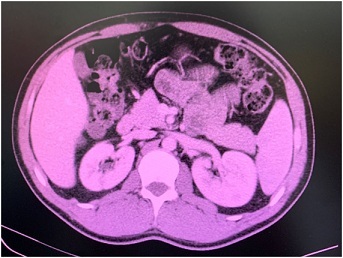

The case reports to a 30-year-old male patient with complaints of an insidious illness, characterized by several years of evolution and marked by a profound deterioration within the previous 3 months. The patient reported episodes of constipation alternated with diarrhea, the presence of a feeling of bloating and occasional vomiting, in the absence of weight loss or any other complaints. The patient denied the existence of any relevant personal, surgical, or familiar history. He underwent an abdominal and pelvic computerized tomography which revealed a discontinuous filling of the Jejunal loops after oral administration of a contrast agent, with a hiatus development between the jejunum and the ileum. This finding was compatible with a left internal Para duodenal hernia (Fig 1 2), without an associated disturbance of the gastrointestinal transit or abnormality of the morphology of the intestinal loops. Additionally, sthe patient was submitted to a colonoscopy and analytical evaluation including measurement of tumor markers. A thorough study of the intestinal transit was also performed, through the administration of an oral contrast agent. These investigations resulted unremarkable.

Figure 1: Oral discontinuous contrast showing left paraduodenal hernia

Figure 2: Appearance of left paraduodenal hernia on CT scan